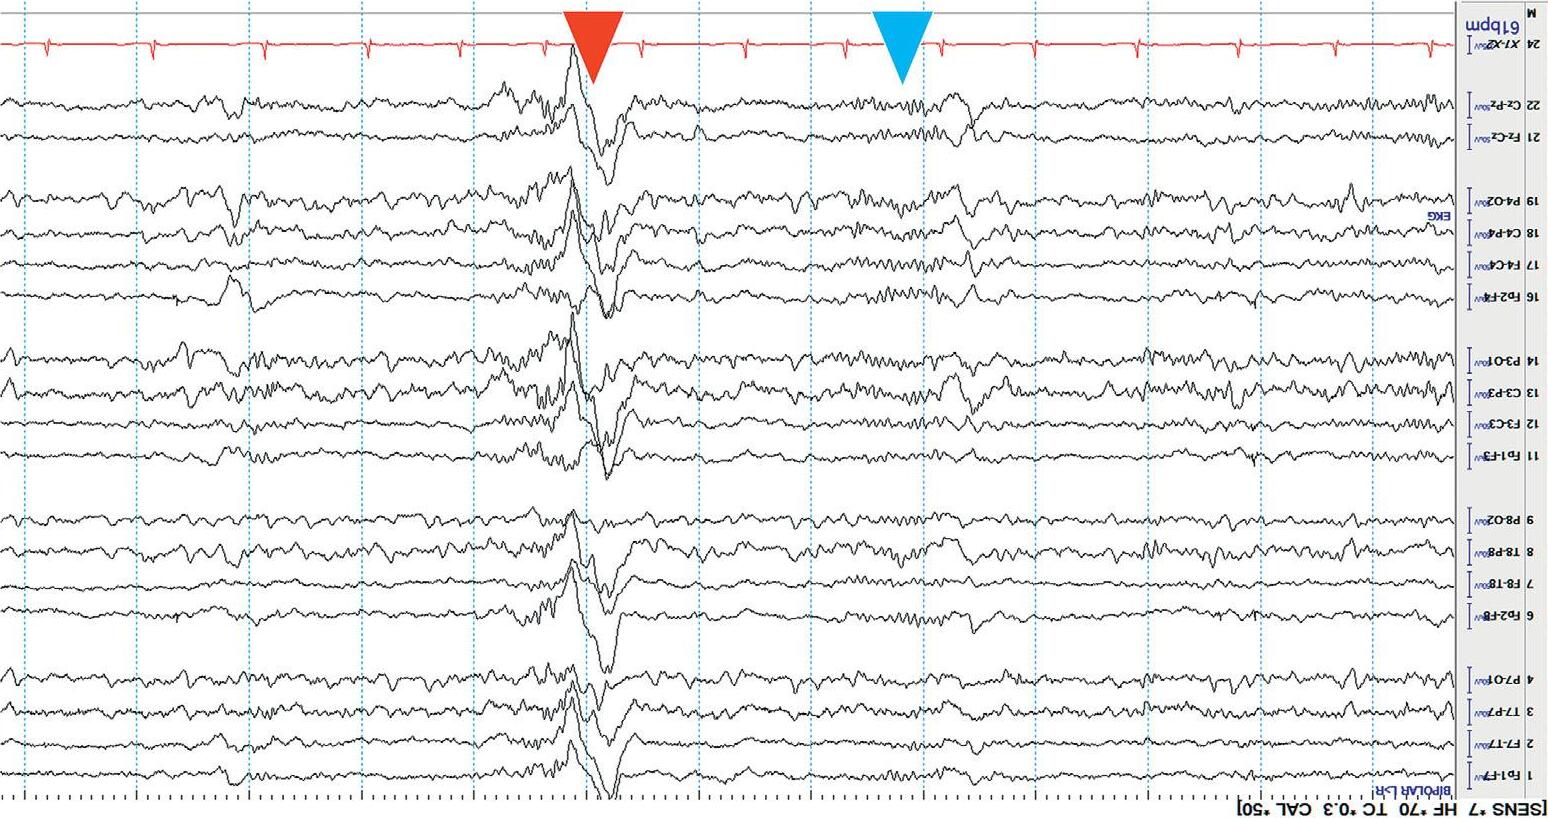

Thekeytolocalizationisanelectrographicprinciplecalleda phasereversal. ThisisasimultaneousbutoppositedeflectionintwoadjacentEEGchannels containingacommonelectrode.Aphasereversalimpliesthatthecortical potentialismaximalatthelocationofthecommonelectrode.

Mostphasereversalsarenegative(><),thoughrarelypositivephase reversals(<>)mayoccur. Figure1.4 showsanexampleoflocalizingafocal sharpwave.

Figure1.4 Localizingasharpwave(blackarrow)throughphasereversaltoelectrodeP8(blackcircle).